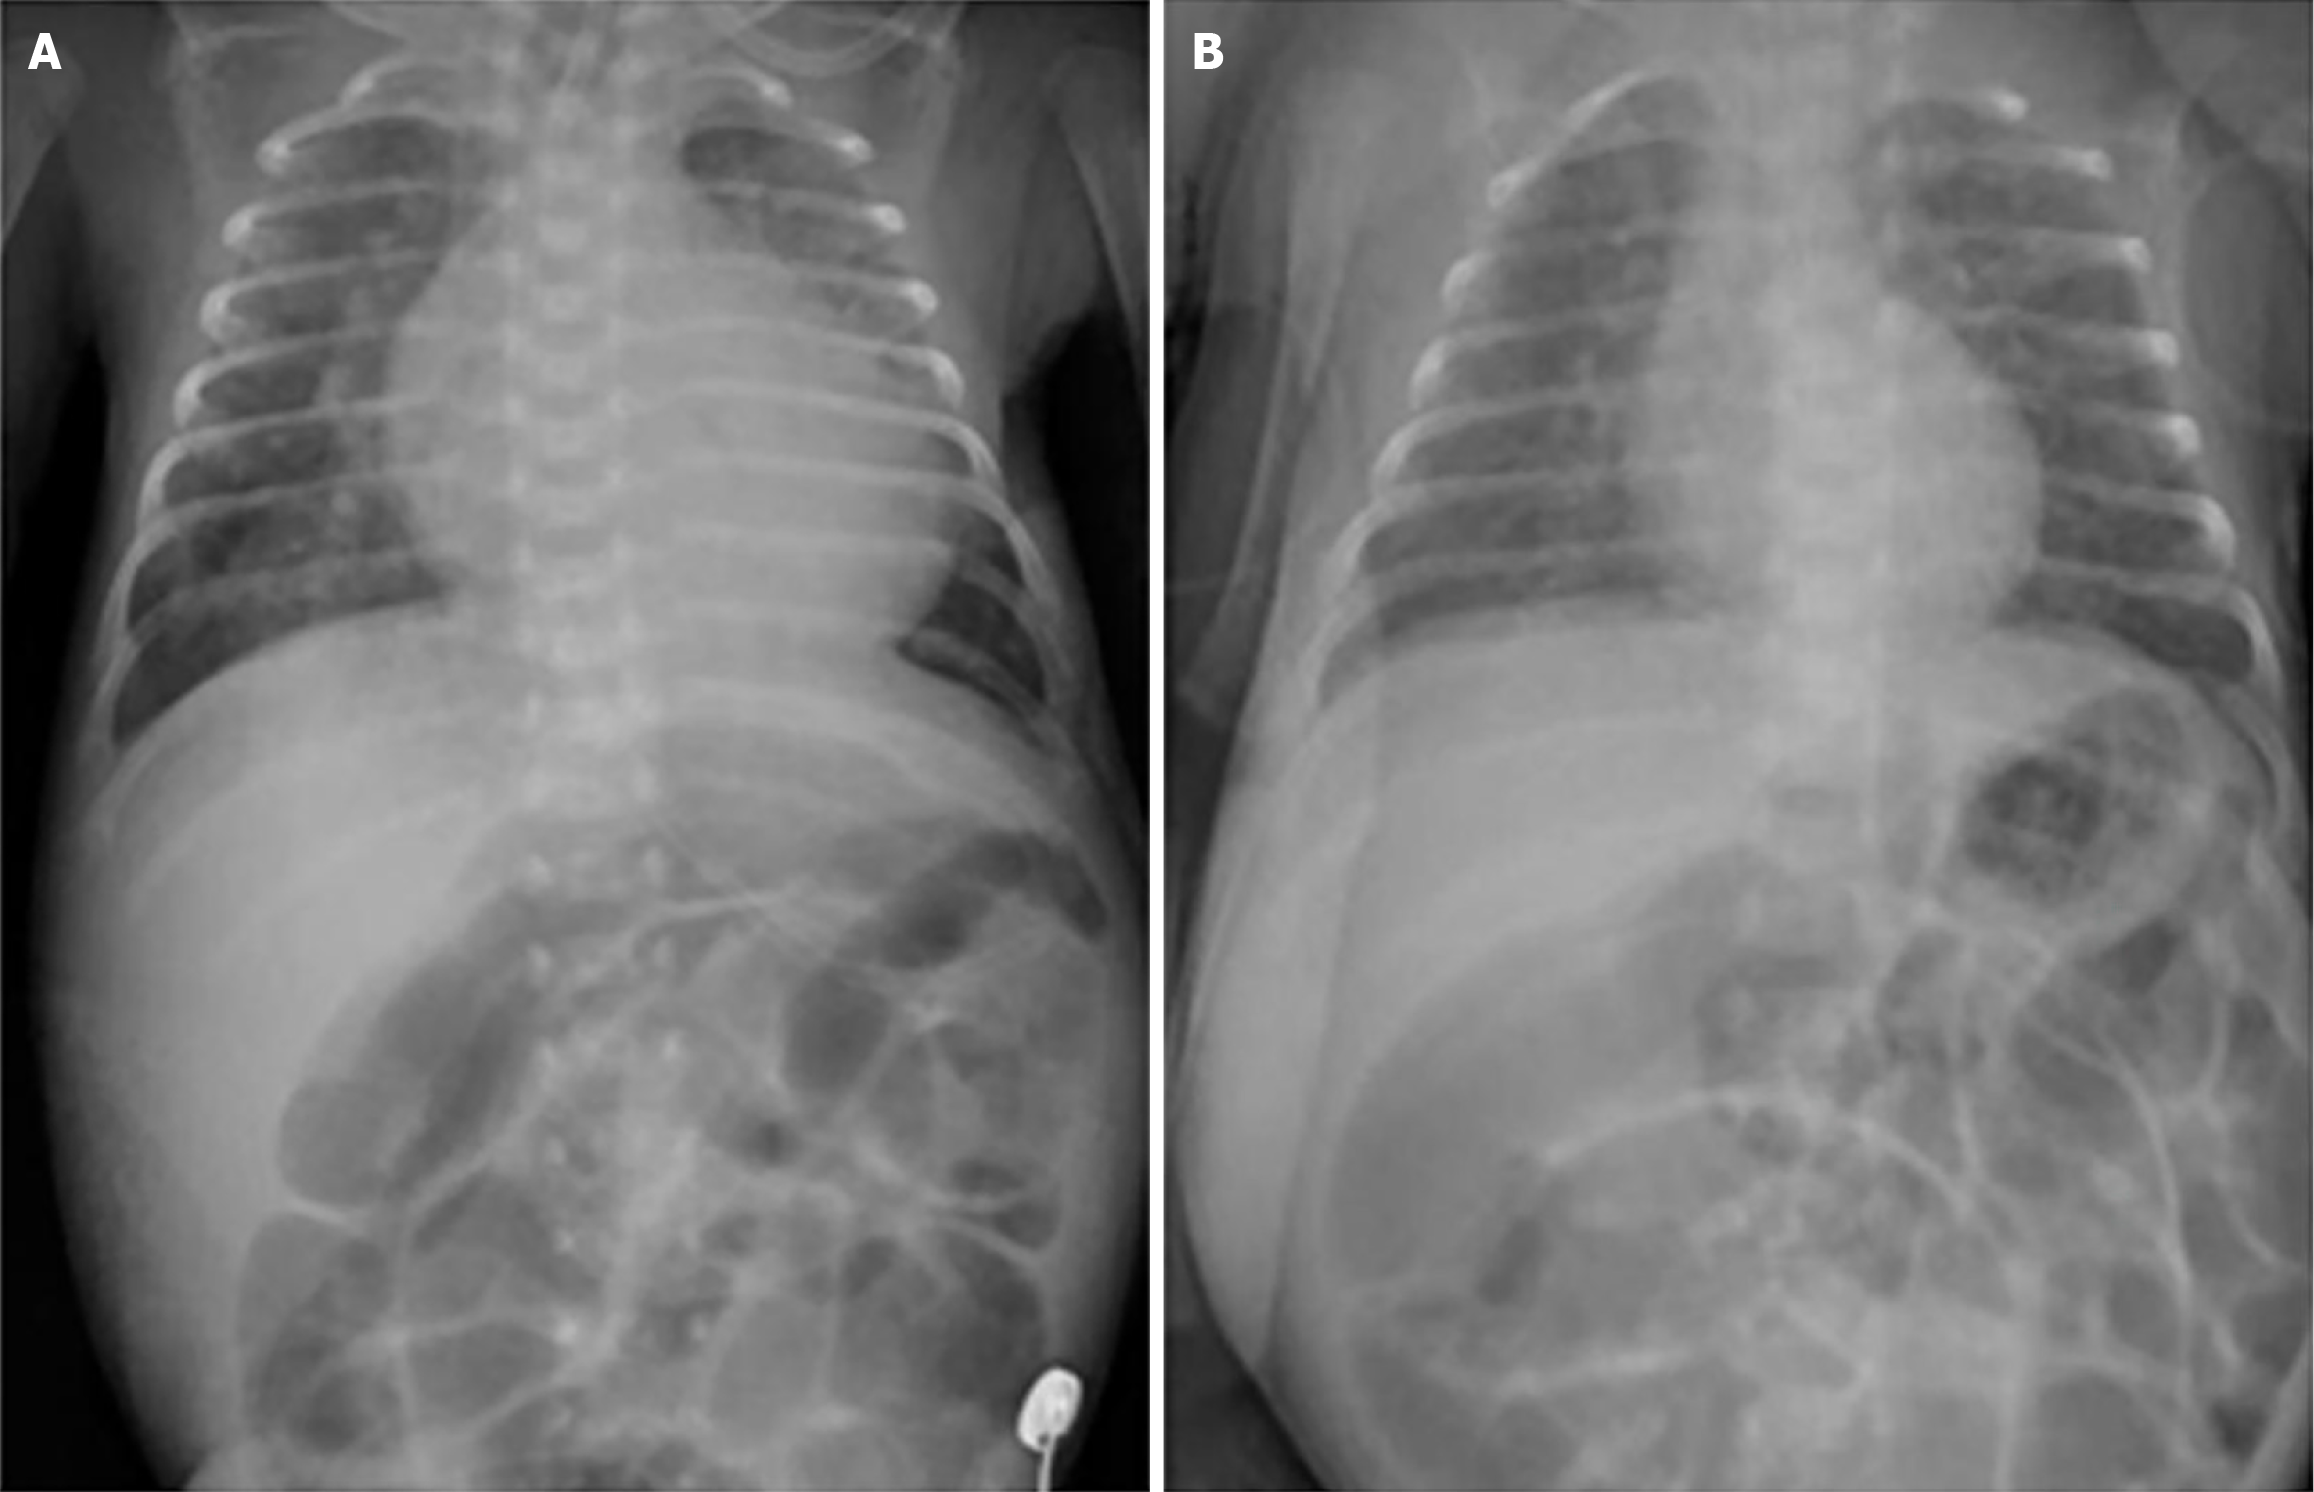

Figure 1 Chest radiography changes before and after levothyroxine treatment.

A: Admission chest radiograph (2 days before levothyroxine) showed cardiomegaly and pulmonary congestion; B: Post-levothyroxine chest radiograph revealed marked improvement.